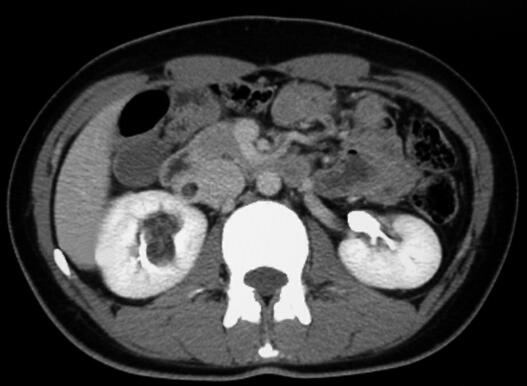

CT平扫:右肾盂旁可见一个不规则团块状混杂密度影,大小4.5cm×2.9cm×1.9cm,最低密度CT值为-40HU。增强扫描病变组织部分明显强化,最高CT值达97HU。增强后显示病变主要位于肾窦,并紧贴肾血管走行,一部分病变组织延伸至肾静脉内,一部分病灶压迫肾盂并与肾实质分界不清,右肾上、中盏受压变形(图1~图4为该肿瘤的部分CT扫描图像)。

图4 增强扫描(排泄期)肾盂及中盏受压变形